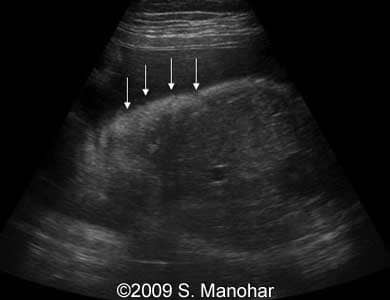

Images 8, 9, 10, 11, 12, and 13: The images shows discontinuities of the skin surface (arrows), a typical sign of the Harlequin type ichthyosis.

8-b

8

9-b

9

10-b

10